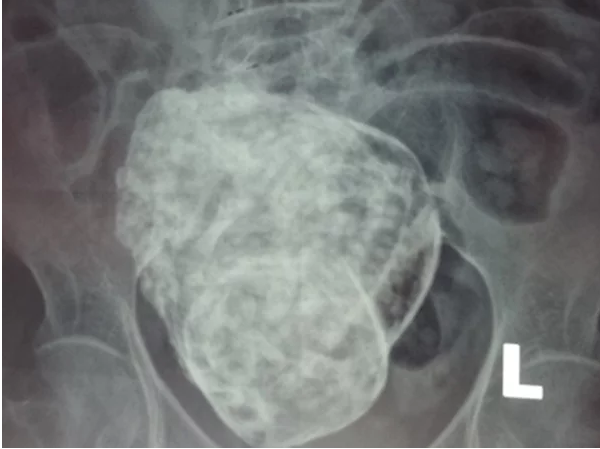

Bà Nguyễn Thị Sáu ở tổ Lộc Phúc, phường Cam Lộc, TP Cam Ranh, tỉnh Khánh Hòa là trường hợp đầu tiên tại Việt Nam được phát hiện mang thai ở tuổi 76. Được biết, sau một thời gian dài cảm nhận thấy đau bụng và có dấu hiệu buồn nôn, trướng bụng, đau thắt lưng và cột sống thì cụ Sáu quyết đến viện kiểm tra.Qua siêu âm và chụp X-Quang, các Bác Sỹ phát hiện trong bụng bà Sáu có một thai nhi đường kính khoảng 20x20cm đã phát triển đầy đủ hộp sọ, cột sống, các xương sườn, xương đùi. Tuy nhiên, thai nhi bị C.h.e.t lưu trong bụng đã gần 30 năm mà bà cụ không hề biết nên thai nhi đã bị vôi hóa (tức hóa thạch).

Hình ảnh siêu âm thai nhi bị vôi hóa trong bụng cụ Sáu.

Cụ Sáu đã được các Bác Sỹ nghiên cứu p.h.ẫ.u. .t.h.u.ậ.t. thai nhi bị vôi hóa trong bụng gần 30 năm.

Theo các nhà chuyên môn, thai “đá” là trường hợp thai trên 14 tuần bị C.h.e.t lưu nhưng không đào thải ra ngoài được, lưu lại trong cơ thể nhiều năm và bị vôi hóa, tức hóa thạch. Với những thai phụ trên 40 tuổi, tỉ lệ mang thai đá cao gấp 5 lần so với những thai phụ dưới 40 tuổi. Trường hợp thai đá nằm ngoài tử cung thì có thể gây biến đổi nguy hiểm.